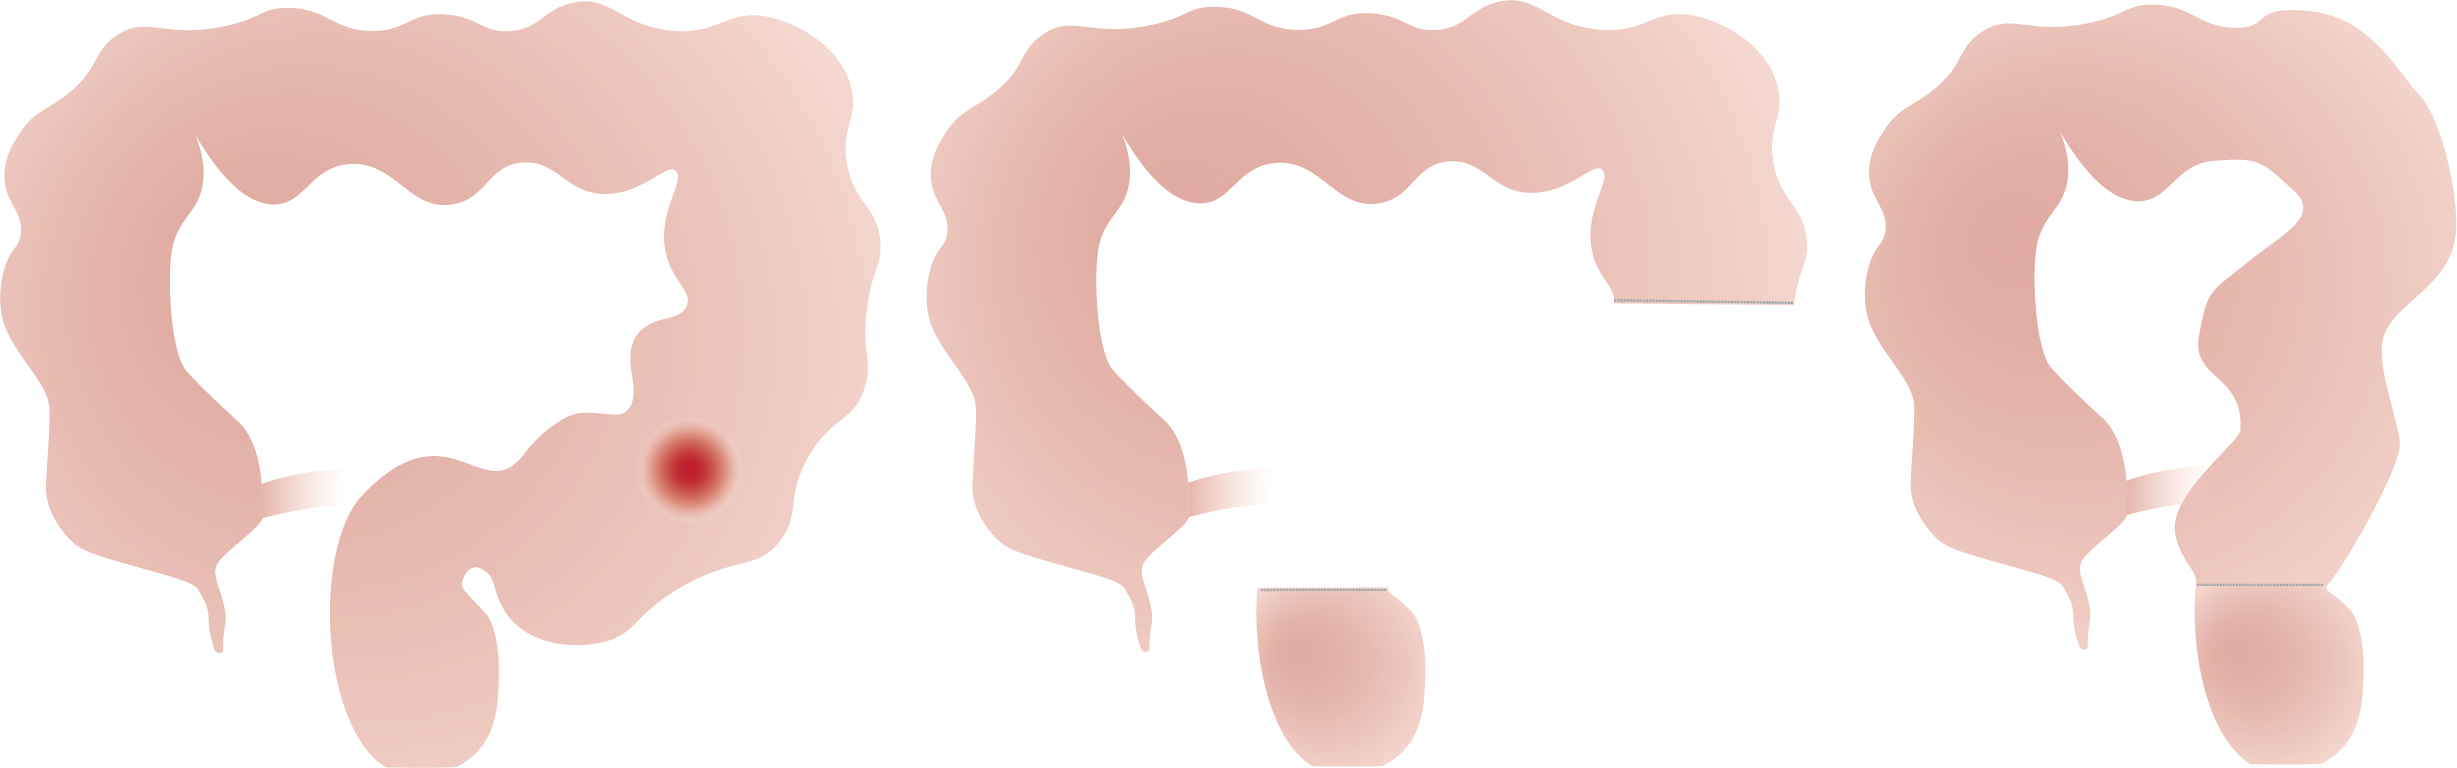

Naargelang de plaats van de aandoening spreekt men van een:

• Linker hemicolectomie (colectomie = verwijderen van dikke darm, hemi = half) en sigmoidectomie (wegnemen van het voorlaatste deel van de dikke darm).

• Rechter hemicolectomie (colectomie = verwijderen van dikke darm, hemi = half).

• Rectum resectie (= verwijderen van de endeldarm zonder de anus).

• Rectumamputatie (= verwijderen van de endeldarm met de anus).

• Totale colectomie (= verwijderen van de hele dikke darm met eventueel dunne darm 'pouch').

Na het verwijderen van het aangetaste stuk darm wordt een nieuwe verbinding gemaakt tussen twee gezonde stukken darm en is het belangrijk dat deze goed gaat genezen.